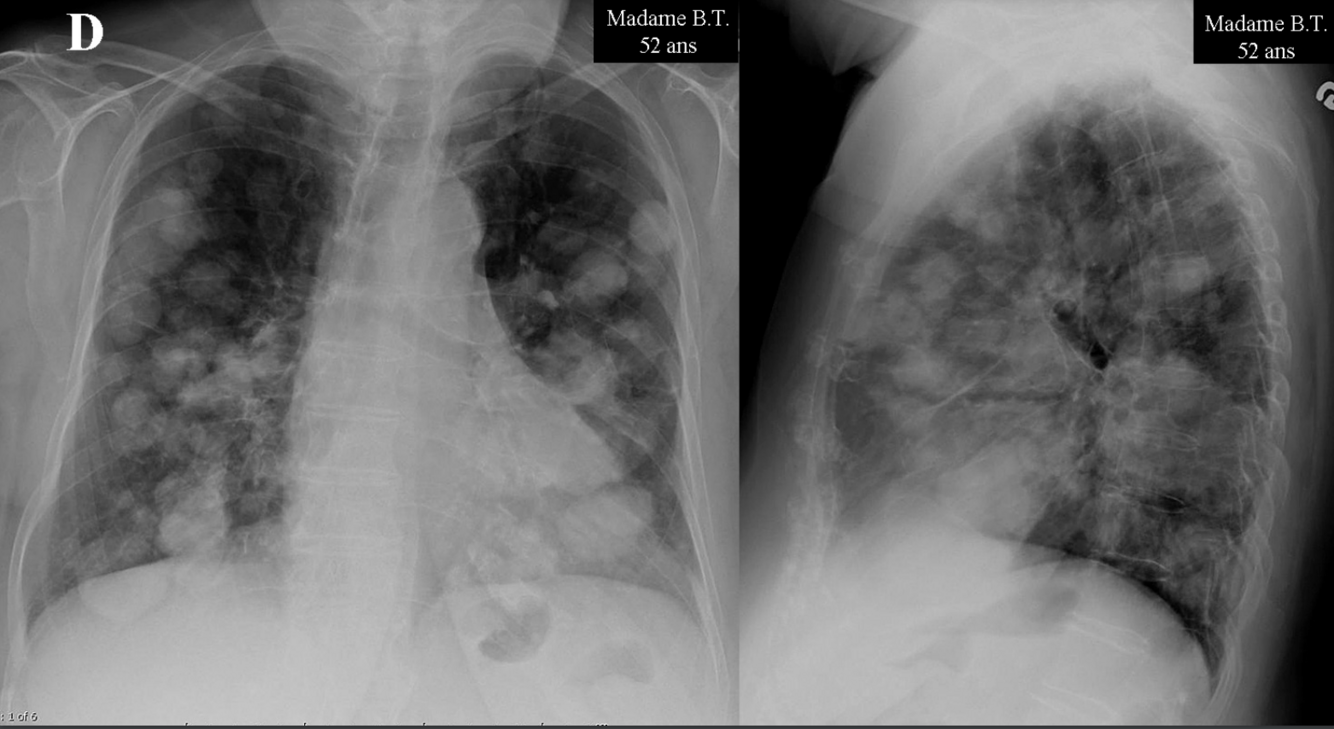

Une femme de 52 ans consulte pour de la toux persistante depuis plus d’un mois. Cette toux l’empêche de dormir dans son lit et elle dort maintenant assise sur le fauteuil du salon afin d’être plus confortable. La dame se dit très fatiguée. Par ailleurs, la patiente ne rapporte pas d’infection des voies respiratoires récentes ou de problèmes digestifs. La patiente n’a jamais fumé et ne prend pas de médications sur une base régulière. Elle dit que la prise de sirop antitussif n’aide pas à diminuer ses symptômes.

Dans le contexte de toux subaigüe sans diagnostic clinique précis, une radiographie pulmonaire est demandée. Quelle est la meilleure interprétation de la radiographie?

A

Métastases pulmonaires diffuses